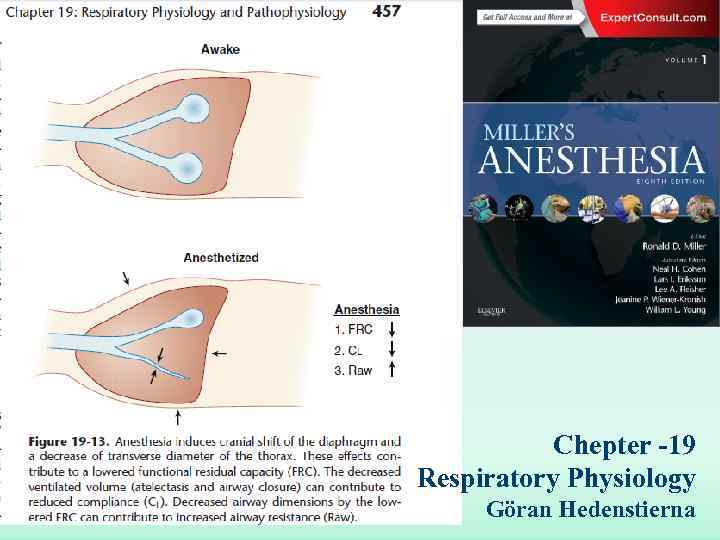

Chepter -19 Respiratory Physiology Göran Hedenstierna

Chepter -19 Respiratory Physiology Göran Hedenstierna